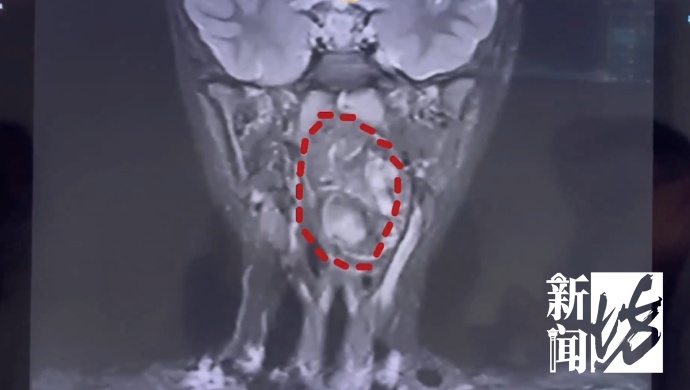

复旦大学附属儿科医院 耳鼻咽喉头颈外科副主任 陈超:我们可以看出它有脂肪,有软骨,这是一对双胞胎,一个是我们正常的人发育成的人,另外一个他可能残留在这个咽旁间隙里面,就发育成了这样的一个畸胎瘤。

医生解释,虽然畸胎瘤绝大多数是良性,但多生于腹腔内。像这样长在儿童咽喉部,而且又这么大的,极其罕见。肿瘤还在长大,如不及时干预,孩子恐有生命危险。

复旦大学附属儿科医院 耳鼻咽喉头颈外科副主任 陈超:6岁男孩的口咽腔大概在8公分左右,这个孩子的肿瘤已经高达6公分多,整个气道已经完全被这个膨大的肿瘤占据了,只有一条黑颜色的线,这是它透气的空间,再让它继续膨胀下来,它首先出现的一个症状应该是呼吸道的梗阻窒息,会出现窒息致死的可能。

雪上加霜的是,由于肿瘤紧贴颈内颈动脉,甚至明显将颈鞘压弯,手术的出血风险极高,这或许也是当地医院没有收治的原因。

最终,历时三小时,这枚6.6乘3.5乘3厘米的畸胎瘤被分为两块,完整切除。术后5天,小亮几乎完全恢复了。